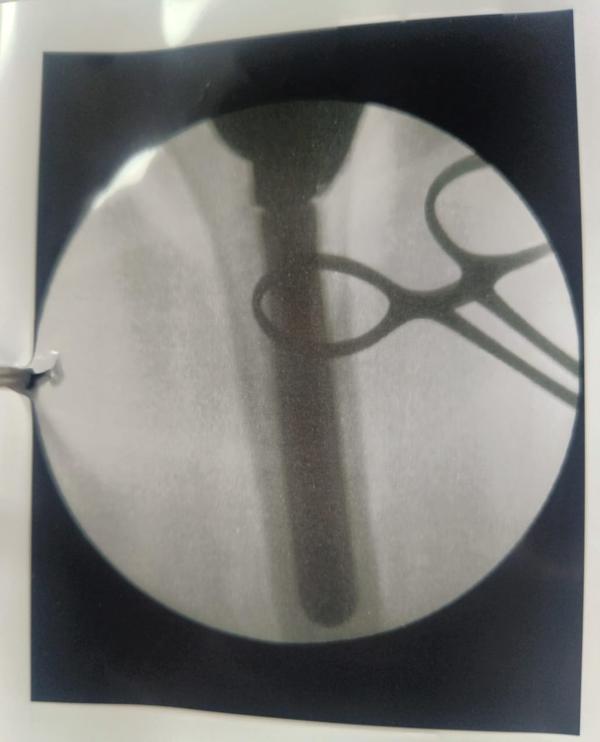

Revision Hip And Knee Replacement

Dr Randive has 25 years experience in Revision Knee and Revison Hip Replacement surgeries. It took him more than 25 years of training hard work and thousands of surgeries to achieve excellence in Revision Knee and Hip Surgeries. He has successfully achieved this milestone through extensive training.